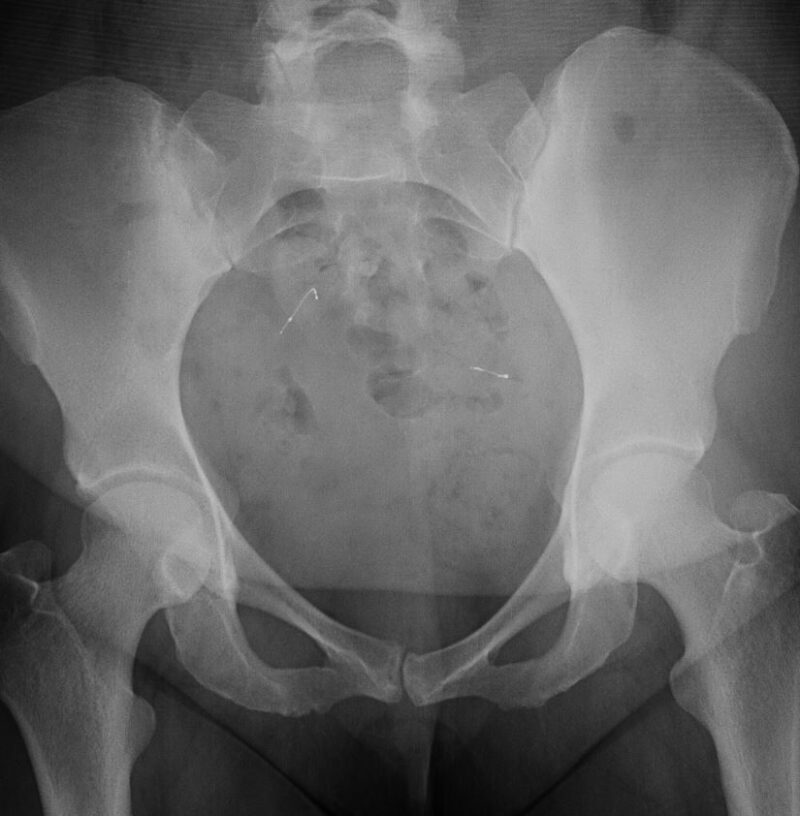

Metal Coils In Fallopian Tubes . Insertion of the essure implant involves the placement of small metal coils in the fallopian tubes to induce their closure. It causes scar tissue to form. Some surgeons make cuts around the fallopian tubes to remove essure coils. Small flexible coils made of fiber and metal are placed in the fallopian tubes, which connect the ovaries to the uterus. Doctors insert the coils with a disposable metal catheter. The catheter goes to the entrance. Essure is a permanent birth control method that involves placing coils in the fallopian tubes to create scar tissue and prevent. The essure device is a flexible metal coil placed inside each of the tubes to the ovaries. Essure is a permanent birth control device that consists of two small metal coils inserted through the vagina into the fallopian tubes (see.